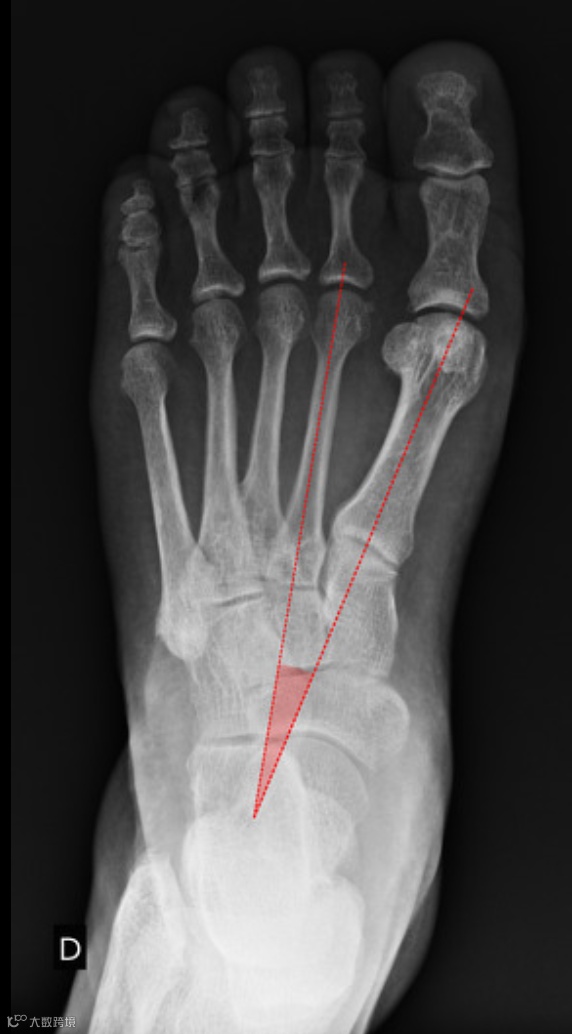

跖骨间夹角(IMA)

第一、第二跖骨干中线之间的夹角

正常值小于9°

辅助诊断:IMA ≥ 10°

若IMA≥10°,结合拇外翻角异常,可辅助诊断。